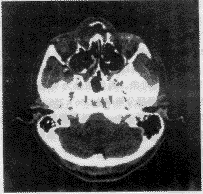

图像由磁光盘输入,CT图像数据的每个像素为12位4096个灰阶,将12位转变成8位256灰阶,调整窗宽窗位。窗宽定为256,窗位为865,调整前后图像如图2、3所示。最后将93层图像逐层拼接成体数据。由于分辨率满足要求,不需要插值。

图 2 调整前图像

图 3 调整后图像